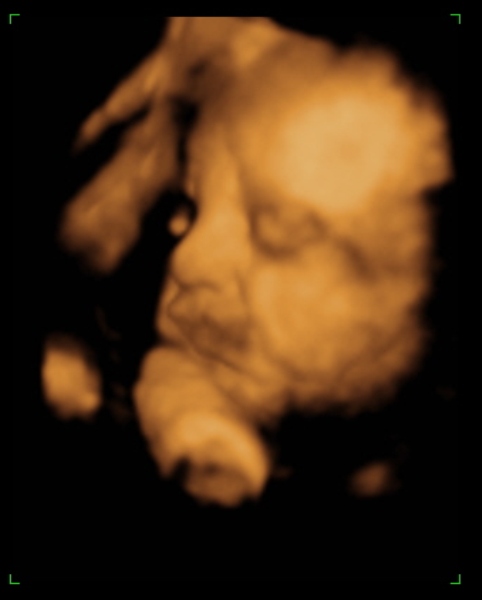

Tegnap megjártuk a 4D-t, nagyon szép husis a kisasszony :lol: persze aludt, nem kommunikált velünk, akármit ettem, ittam, csináltam. :lol: De azért féloldalasan aludt, úgyhogy csak láthattuk, volt mosoly, ásítás, fintor :lol: :lol:

Ja, és itt is megállapították, hogy nagy a talpa :lol: :lol: :lol: És a fejecskéje is, úgyhogy azt mondták majd megdolgoztat szülésnél, gondoltam "tök jó" :lol: :roll:

Ja, és a képek lemaradtak :D

Kép mosolygom:)

Kép ásítok, UFO nyitott szemeimmel:))))

Kép profilból

Kép nagy tapppppancsom:)

Persze a kis keze mindenhol ott van :lol: Bocsi, ha picit sok voltam :oops: 8)